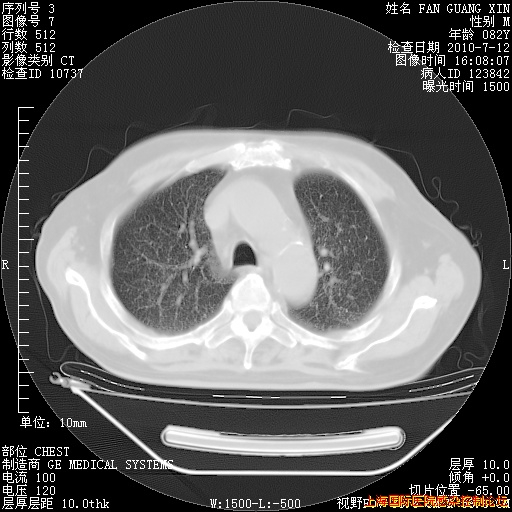

补发6月12日肺部CT肺窗

6月12日肺窗